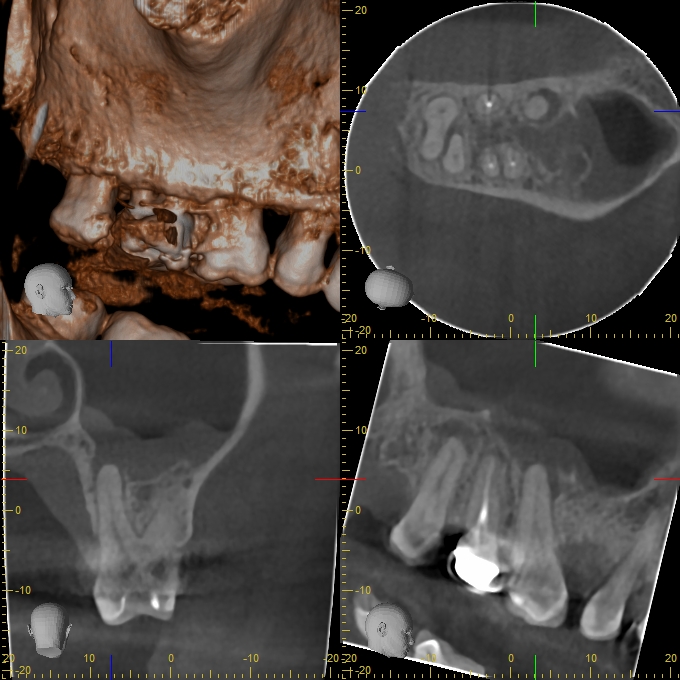

XYZView_20140429_111903

680 × 680

2D vs. 3D (XXVII)